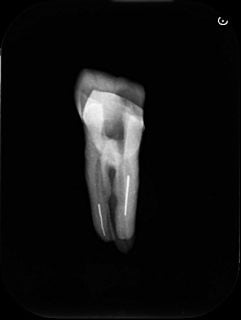

下記は、破折ファイルが折れこんでいる歯のレントゲン写真です。白く線状に見えるのが破折ファイルです。(Photo.2)